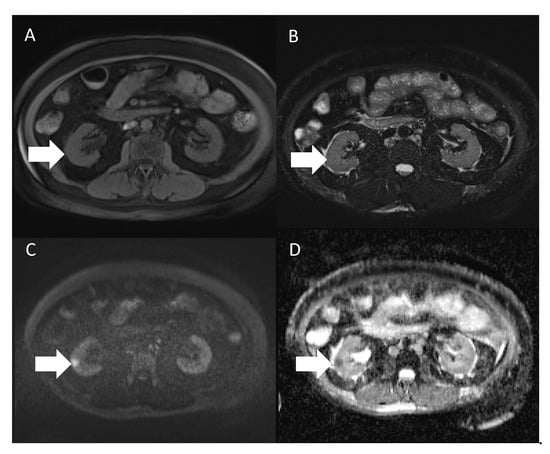

| 8 | 56/F | None Incidentally found | ESRD, HTN, diabetes, hyperlipidemia | Right lateroposterior cortex of the lower pole | 1.3 cm | US: Lesion detected MRI: Iso-intensity in the T1- and T2-weighted images and low ADC value CT: Early enhancement, suspecting RCC | HV | Laparoscopic nephroureterectomy | Free of disease 17 months after surgery | Our case |